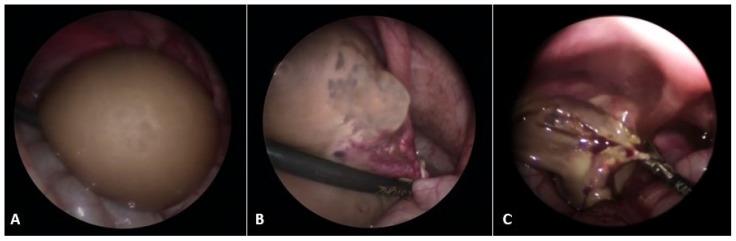

The majority of abdominal masses in female children derive from the ovaries. Ovarian masses in pediatric populations can vary from simple functional cysts to malignant neoplasms. Their incidence, clinical presentation, and histological distribution vary across age groups. In the assessment of ovarian masses in children, the primary aim is to determine the probability of malignancy, as the treatment approaches for benign and malignant lesions are significantly distinct. The primary imaging tool for evaluating ovarian cysts and masses is ultrasound, which can assess the size, location, and characteristics of masses. Magnetic resonance imaging (MRI) or computed tomography (CT) may be used for further evaluation if ultrasound findings are inconclusive or if malignancy is suspected, especially in older adolescents. Serum markers may be considered in older adolescents to help assess the risk of malignancy, though it is less useful in younger populations due to normal developmental variations. Many functional ovarian cysts, especially those detected in fetuses or infants, often resolve spontaneously without intervention. Surgical intervention is indicated in cases of large cysts that cause symptoms, or if there are concerns for malignancy. Common procedures include primarily ovarian sparing laparoscopy or laparotomy. Complications like torsion, rupture, or hemorrhage may require urgent surgical intervention. Treatment should be performed in specialized centers to avoid unnecessary oophorectomies and ensure the best possible outcome for the patient. This comprehensive review aims to provide an overview of the evaluation, diagnosis, and treatment of ovarian masses in the pediatric population. Emphasis is placed on the particularities of the lesions and their management in relation to age subgroups.

女童腹部肿块大多源于卵巢。儿科人群中的卵巢肿块种类繁多,从单纯的功能性囊肿到恶性肿瘤都有。其发病率、临床表现及组织学分布因年龄组而异。在评估儿童卵巢肿块时,主要目的是确定恶性的可能性,因为良性和恶性病变的治疗方法有显著区别。评估卵巢囊肿和肿块的主要影像学工具是超声,它可以评估肿块的大小、位置和特征。如果超声检查结果不明确或怀疑有恶性可能,尤其是年龄较大的青少年,可能会使用磁共振成像(MRI)或计算机断层扫描(CT)进行进一步评估。年龄较大的青少年可考虑检测血清标志物以帮助评估恶性风险,不过由于正常发育变异,血清标志物在年幼儿童中作用较小。许多功能性卵巢囊肿,尤其是在胎儿或婴儿中发现的囊肿,常常无需干预即可自行消退。对于引起症状的大囊肿或怀疑有恶性可能的情况,需进行手术干预。常见手术主要包括保留卵巢的腹腔镜手术或剖腹手术。扭转、破裂或出血等并发症可能需要紧急手术干预。治疗应在专业中心进行,以避免不必要的卵巢切除术,并确保患者获得最佳治疗效果。本综述旨在概述儿科人群卵巢肿块的评估、诊断和治疗。重点在于病变的特殊性及其在不同年龄亚组中的处理。